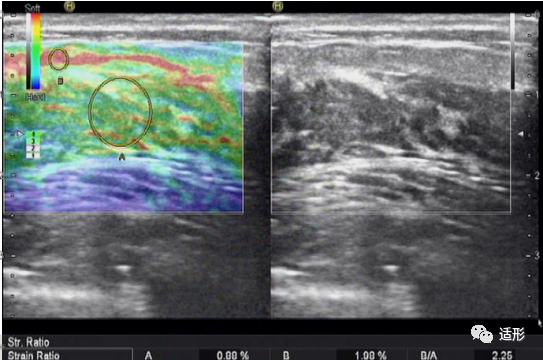

NML的弹性表现与病变的病理类型有关。恶性NML的病变硬度高于良性NML。根据病变应变式弹性成像(SE)的弹性图像表现,可利用5分评分法来评价NML的良恶性。良性NML病变较恶性NML病变软,评分多为1-3分(图1)。恶性NML较良性NML病变硬,评分多为4-5分(图2) 。结合常规超声与5分评分法评价NML,诊断恶性NML的准确性可达83.1%。另外,也可应用病变组织与皮下脂肪组织的弹性应变率比值来鉴别NML良恶性。Qu等以4.07为应变率比值截断值时,其诊断恶性NML的准确率可达95.5%。

图1. 44岁女性,超声提示乳腺内非肿块型病变,呈低回声。弹性评分(右侧)为2分,应变率比值为2.25. 病理:纤维囊性变